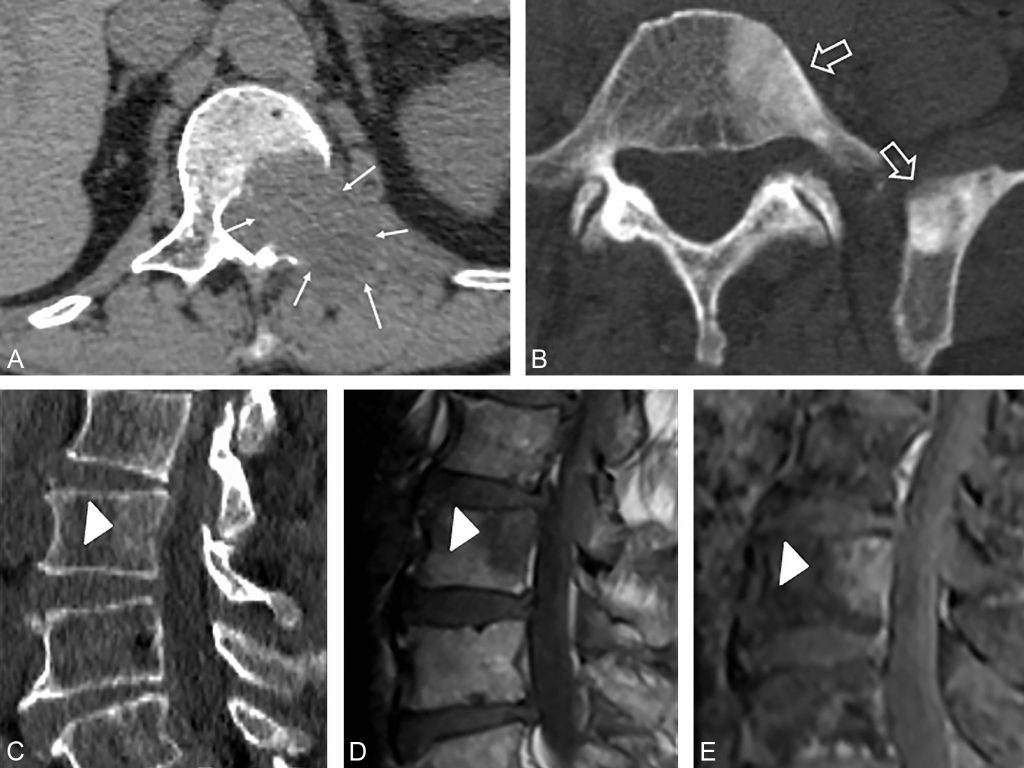

Fig. 88.1 Exemple en IRM de métastases osseuses.

(A) Métastases ostéolytique du corps vertébral de T12 avec envahissement des parties molles et de l’espace épidural chez un patient ayant un cancer du poumon. (B) Métastases ostéocondensantes du corps vertébral de L5 et de la partie postérieure de l’aile iliaque gauche chez un patient ayant un cancer de la prostate. (C à E) Métastase de cancer du sein dans un plan sagittal très discrètement condensante de la partie postérieure du corps vertébral de L4 (C) parfaitement visualisée en IRM en hyposignal T1 (D) et rehaussée sur la séquence T1 Fat Sat après injection de produit de contraste (E).

Source : CERF, CNEBMN, 2022.